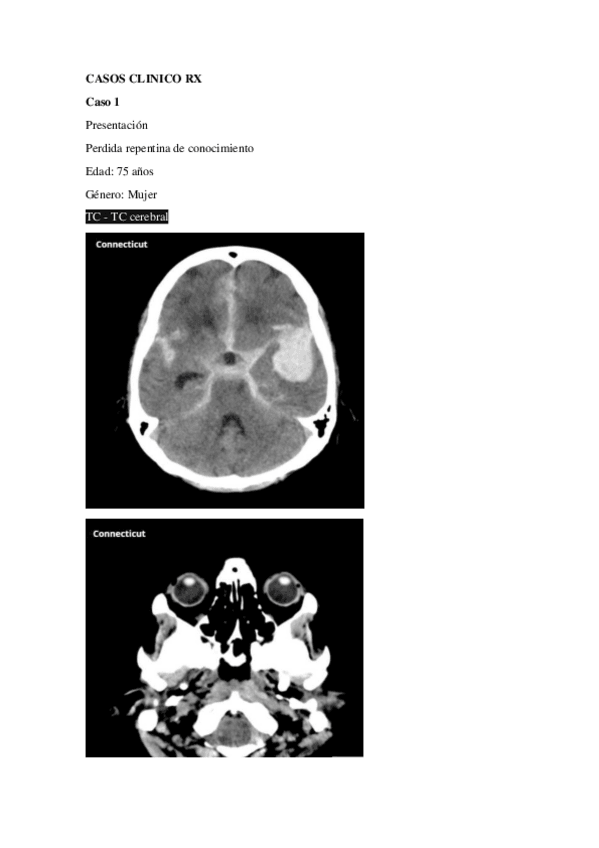

Apuntes - RESUMEN-PARA-RX.pdf

Apuntes - Radiologia.pdf

33 páginas